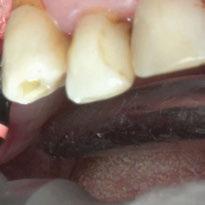

A partir del estudio radiológico y de las imágenes fotográficas podemos observar edentulismo de 17, 15, 14, 12,

25, 26, 28, 37, 38, 47 y 48. Presentaba corona desajustada en 13 con extensión en 12, implantes en 35-36, 45-46, con coronas ferulizadas en 35-36, 45-46, y dientes anteriores superiores con enfermedad periodontal Grado IV.

El paciente presentaba biotipo periodontal grueso, con márgenes asimétricos, con recesiones gingivales a nivel de 11 y 13 y pérdida de tejidos blandos interproximales.